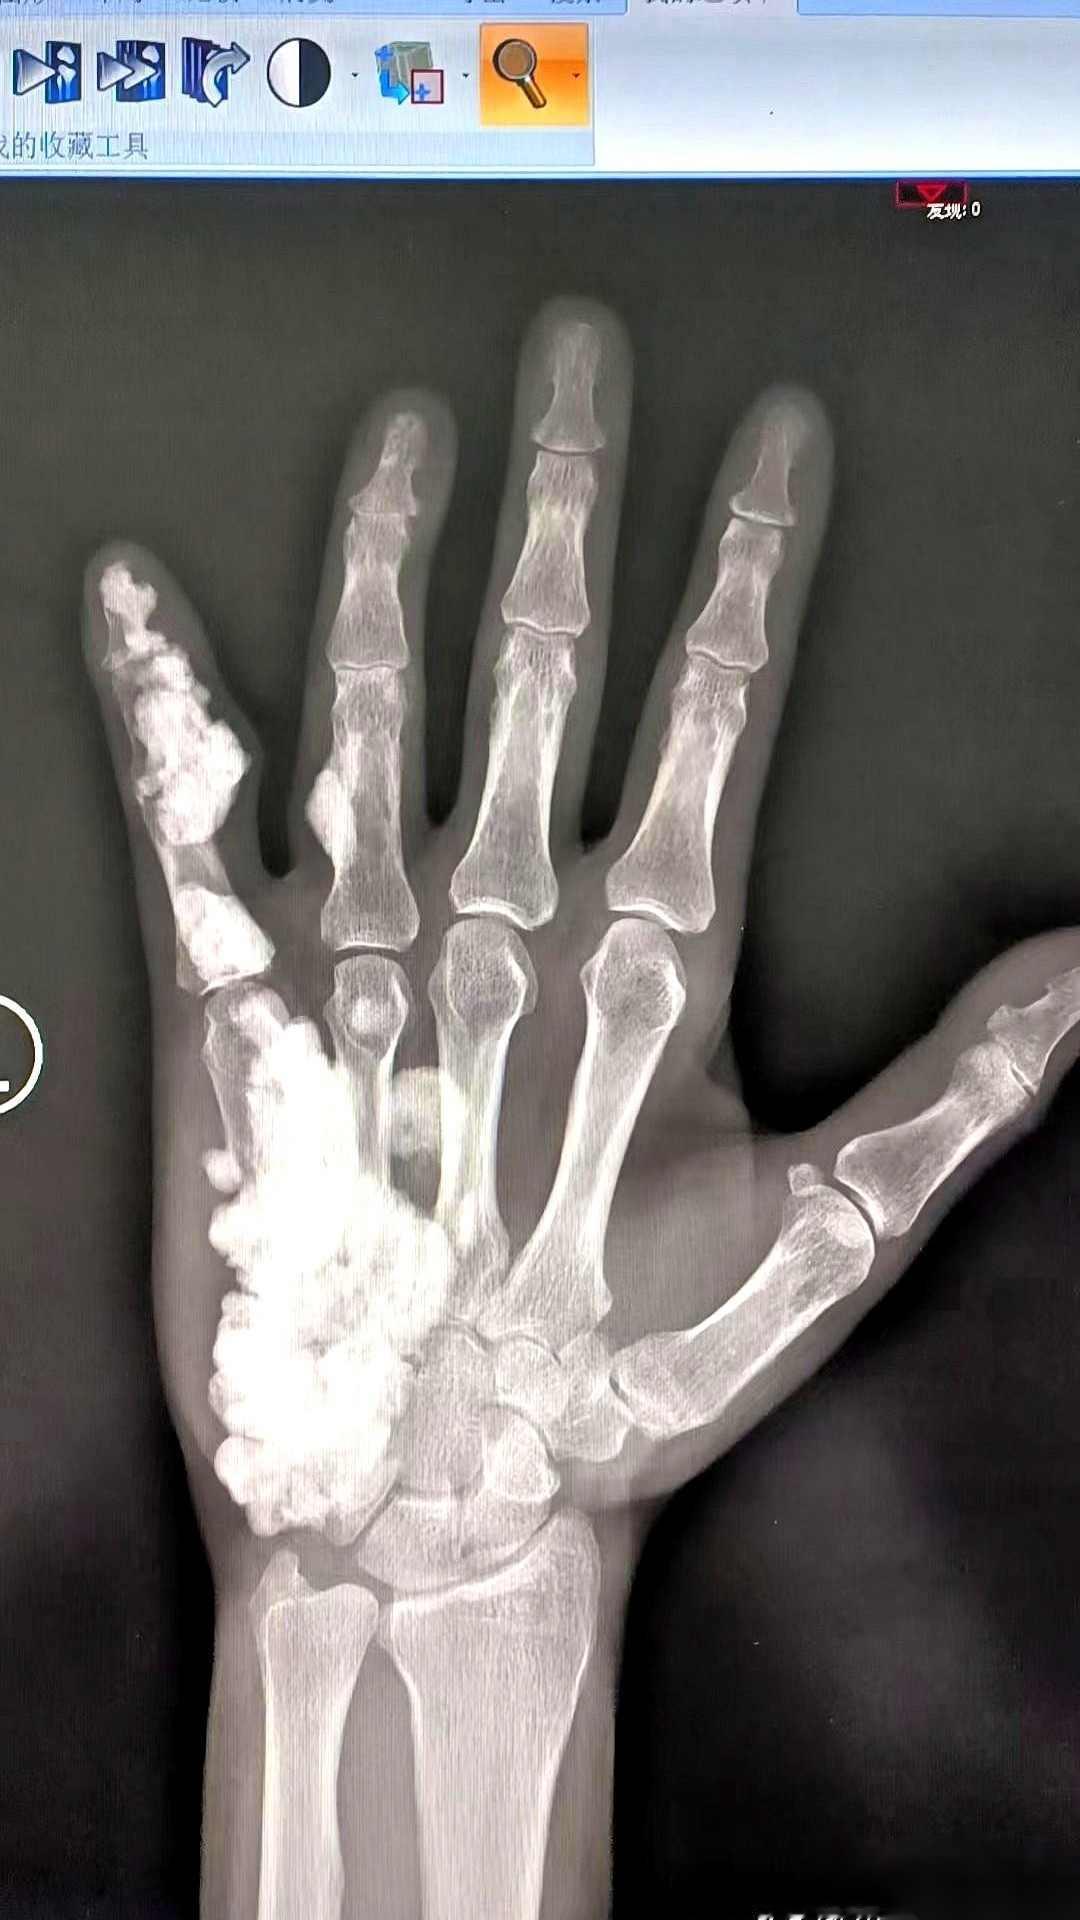

17岁,左手疼了整整10年。拍了个片子,我人都看傻了。医生把X光片递过来,我盯